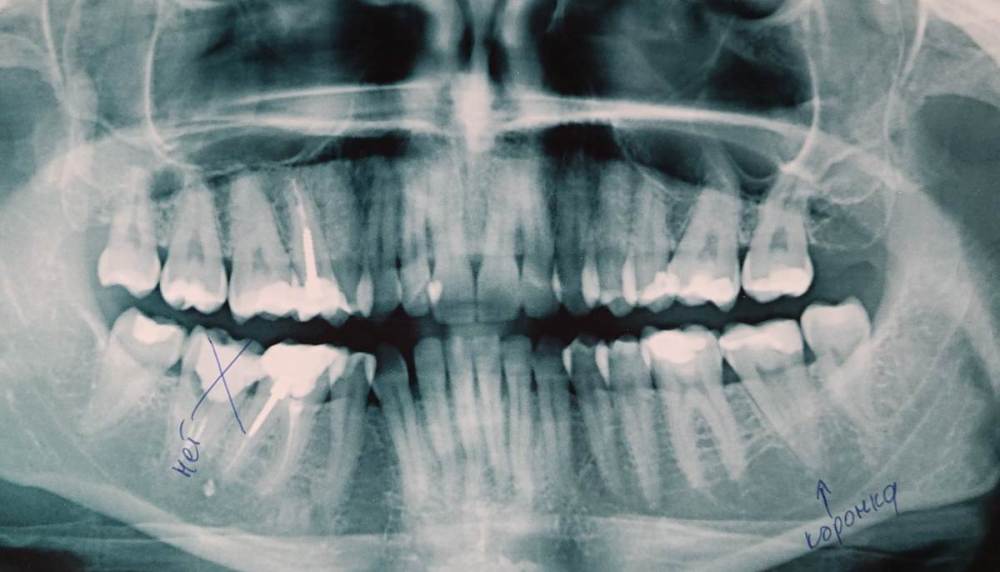

Добрый день.  Имеются восьмерки ,все в приличном состоянии, еще когда то запломбированные, не кривые, не больные. Так получилось что на нижней челюсти с одной стороны на семерку нужно ставить коронку( откололась стеночка) а с другой стороны семерки нет нужно имплант, все остальные зубы на месте. Сейчас я занимаюсь коронкой , поставили вкладку хожу пока с временной коронкой, и вот врач ортопед перед установкой коронки говорит надо вырвать восьмерку ,что бы было больше место для коронки.  Не понимаю зачем удалять нормальные восьмерку? Как коронка может стать больше , если она одевается на мой сточенный зуб?  Для чего ему нужно место?

На слепках зуб семерка спиленный, восьмерка видна..

Обьясните действительно нужно удалять? И для чего?